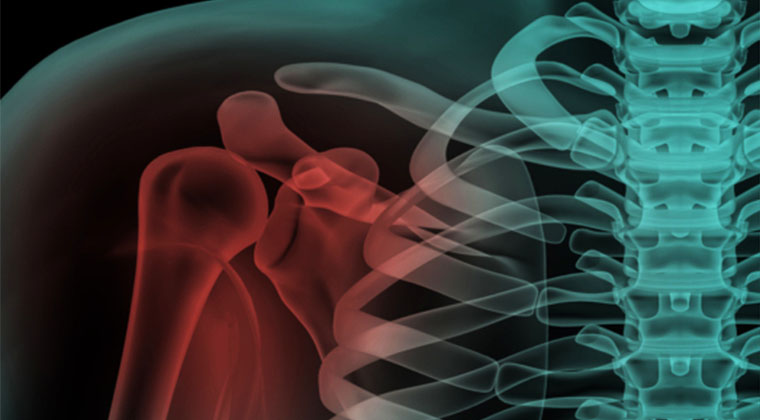

Traumatismele umărului

Cele mai frecvente leziuni ale umărului

Cu ajutorul RMN, diagnosticul este precis, rapid si non-invaziv